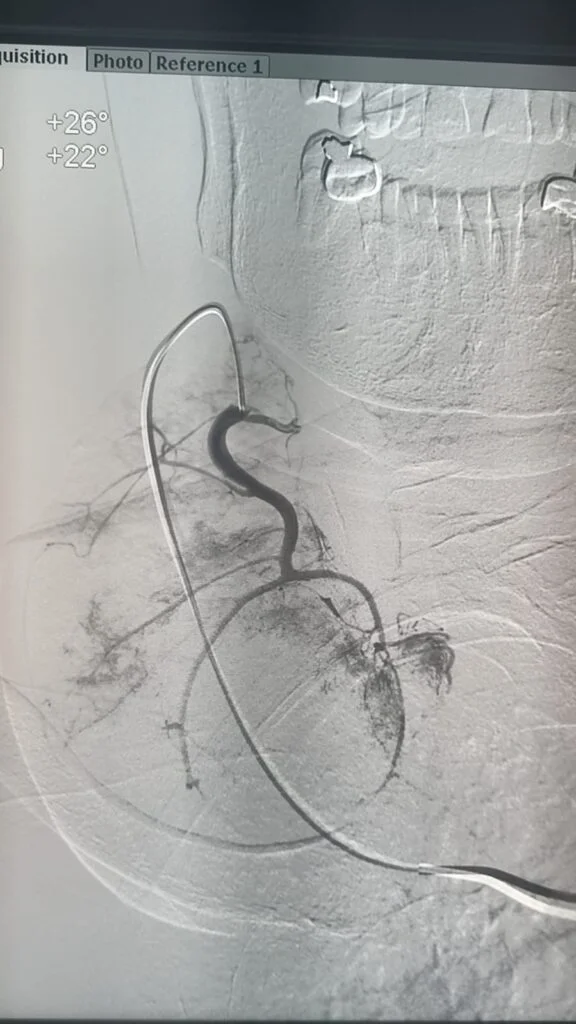

فى إنجاز طبى غير مسبوق داخل مصر، بل و على مستوى الشرق الأوسط، أعلن الدكتور محمود عبد العزيز غلاب – استشارى الأشعة التداخلية – عن نجاحه فى إجراء أول حالة من نوعها فى الأسكندرية لعلاج تضخم الغدة الدرقية عن طريق القسطرة الشريانية، و هو أسلوب حديث تم نقله من اليابان بعد تدريبه فى واحدة من أرقى الجامعات اليابانية المتخصصة فى مجال الأشعة التداخلية.

تعد هذه الحالة الأولى من نوعها التى يتم فيها الدخول عبر القسطرة الشريانية إلى الشرايين المغذية للغدة الدرقية في الإسكندرية.

المريضة، و هى سيدة تبلغ من العمر 81 عامًا، كانت تعانى من تضخم شديد بالغدة الدرقية تسبب فى ضغط على القصبة الهوائية، مع تعدد النتوءات داخل الغدة، إلى جانب معاناتها من أمراض بالقلب حالت دون إمكانية خضوعها لأى جراحة. و بعد رفض حالتها من قِبل أكثر من استشارى جراحة نظراً لخطورة التدخل الجراحى، كان الحل الوحيد هو اللجوء إلى الأشعة التداخلية.

و بسبب كبر حجم الغدة و تعدد النتوءات فيها، لم يكن التردد الحرارى هو الخيار الأمثل، و عليه و بالتنسيق مع الدكتور محمد جلال الغاوى استشاري الغدد الصماء. فقد قام الدكتور محمود غلاب أسلوبًا بالتدخل عبر الحقن بالقسطرة الشريانية، و هو ما مكّن من غلق الشرايين المغذية للنتوءات و بالتالى تقليص حجمهم و تحسين الأعراض بشكل ملحوظ.